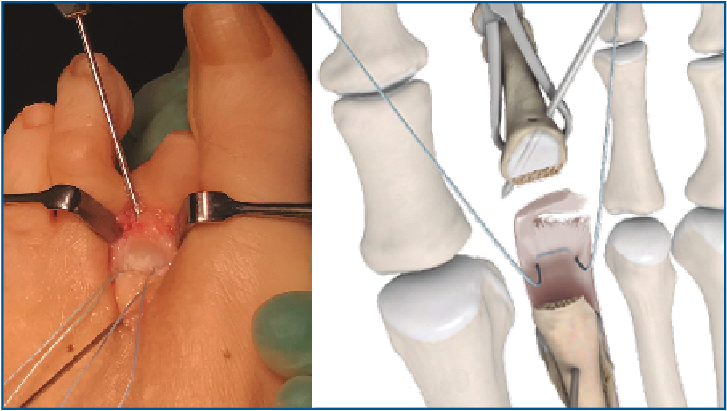

6. Retiramos el distractor y la agK de la falange, y realizamos 2 pequeños túneles de dorsal a plantar en la base de F1 con una broca o agK de 1,2 mm (Figura 10). Estos pueden disponerse cruzados o en paralelo. Aunque la disposición paralela pudiera teóricamente debilitar la base de F1 al ser prácticamente subcondrales, realizarlos cruzados tiene la desventaja de poder interferirse en el pase de las suturas. A través de estos túneles recuperamos las suturas preparadas en el extremo distal de la placa, de plantar a dorsal (Figura 11 y Vídeo).

Figura 10. Doble tunelización en base de F1.

Figura 11. Recuperación de las suturas de plantar a dorsal, a través de los túneles de F1.